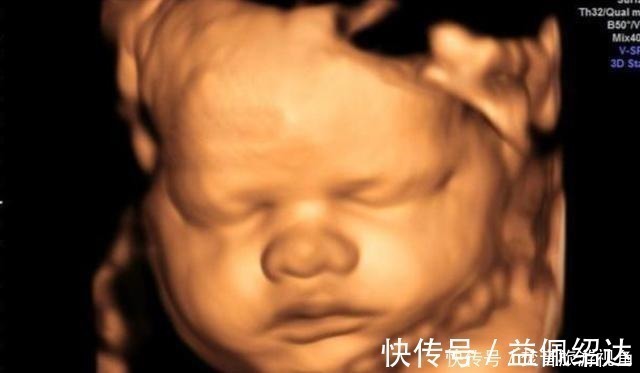

陈女士今年三十三岁,孩子刚刚出生,她非常的开心。别看她如今很坦然,在怀孕期间确实万分小心,对吃的都非常的在意,生怕自己一个不在意对胎儿的身体造成危害。在孕中后期的时候,为了排除更多先天畸形等症状,陈女士在医院做了四维检查。

第一次做检查时,胎儿的脸部、身体都看得非常的清楚,让陈女士感到了很大的安慰。值得一提的是,孩子的一只手伸出了一个手指,非常的可爱。让人没想到的是,第二次检查时,孩子的手指伸出了两根,第三次手指变为了三根,最后一次检查,孩子的手指就变成了四根。